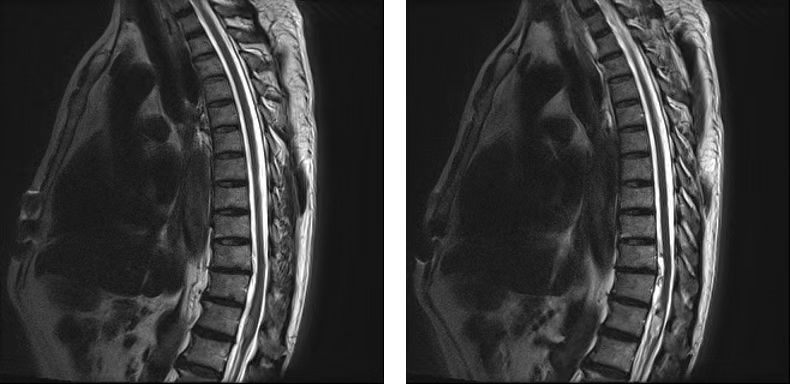

患者入院后MRI检查发现发现患者的胸12节段存在硬膜下髓内占位出血性病变,经治疗小组及科内讨论后病因诊断难以确定。经我院神经外科许刚教授会诊后,高度怀疑脊髓血管畸形,建议行脊髓血管CTA成像检查。这是一种比较罕见的隐匿性脊髓病变,常导致患者出现下肢活动受限。经血管CTA成像及造影检查,结果提示阴性,未见有脊髓内血管畸形,可以排除血管畸形动静脉漏的诊断。但患者症状还是比较严重,疼痛仍然剧烈,长期的睡眠不好,患者也出现焦虑等精神症状,诊断陷入僵局,怎么办?

王栋教授和神经外科周乐教授仔细分析了患者的病史、症状、详细查体体征、所有检查结果,考虑1.脊髓圆锥部位的髓内肿瘤/髓内血肿应该属于第一诊断;2.腰椎(L5)滑脱属于第二诊断;3. 腰椎间盘突出症属于第三诊断。分析患者腰部及左下肢的疼痛与第一诊断密切相关。但脊髓内没有血管畸形,自发出血几乎不可能,最大可能应该是脊髓内肿瘤的出血压迫圆锥神经,引起患者的急性症状,但这样的解释也不能确定。

经过积极的术前评估和详细的手术计划,以及和患者及家属的充分沟通,最后决定进行硬膜下髓内占位病损探查/切除手术。由王栋教授及周乐教授共同主刀,秦杰副教授和欧阳鹏荣主治医师担任助手,麻醉科李芳教授、郑娟医师保驾护航,手术室曲文梅护士等紧密配合,应用高清显微镜进行脊髓病变探查切除手术,全程神经电生理监护。手术中发现T12平面脊髓圆锥左侧明显膨隆,提示病变所在部位确定,分离开圆锥神经束状结构后,发现杏仁大小的棕黄色血肿,在血肿清除后,发现黄豆大小的瘤样组织,没有发现局部髓内血管的畸形及出血,手术顺利圆满完成。探查切除手术证实了术前的分析判断,术后次日,患者腰痛和腿痛症状立即消失,重拾了丢失已久的睡眠和对生活的信心。